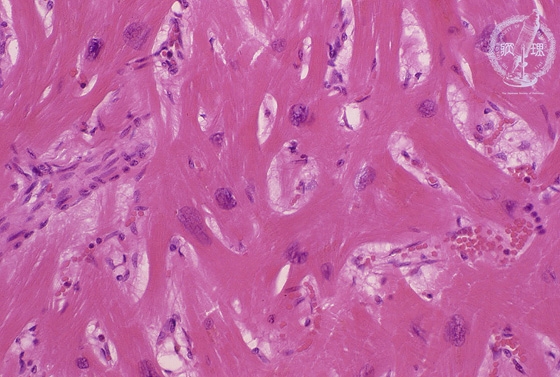

Microscopic image (HE, high power view): Microscopically, hypertrophic cardiomyopathy shows marked myofiber disarray within the ventricular septum.